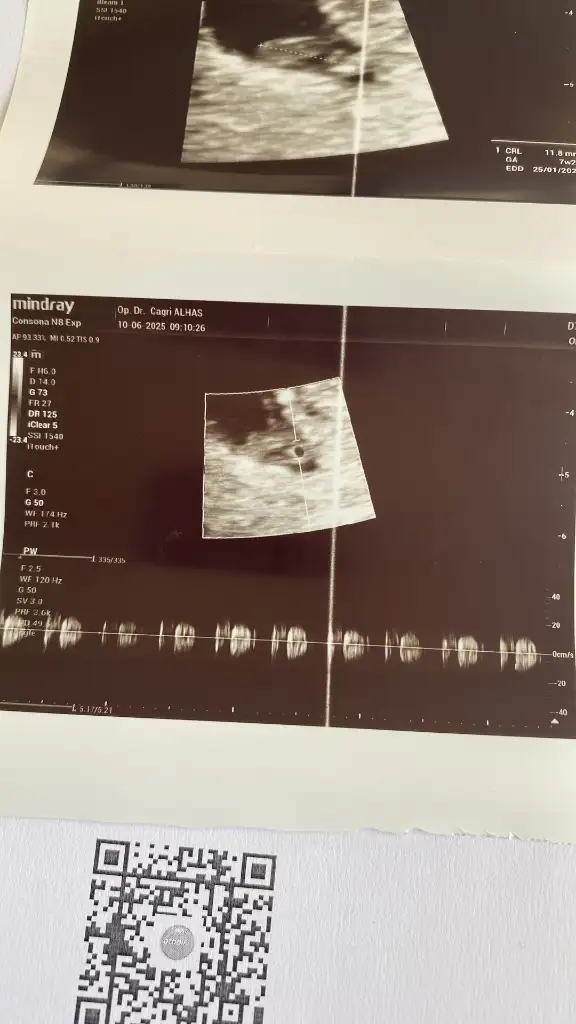

Önceden kimyasal ve boş gebelik geçmişim var,biraz riskli gruptayım diye bakıyorlar. 6+4 deyim. Kalp için gideceğiz bakalım kısmetseAaa hala neden baktırıyorsun ki betaa. Ben 14 mayısta transfer oldum 26 mayıs test günümdü. En son 28 inde baktırdım bida baktırmadım. Kalp atışı için mi gideceksin sende. Kaç haftalıksın

Geldik bizde şimdi hastaneye bekliyoruzzzGünaydın teyzesiiiiikalp atışını duyduk. 6+4 de . Sen gittin mi

Çok sevindim gözünüz aydııınnGünaydın teyzesiiiiikalp atışını duyduk. 6+4 de . Sen gittin mi

Çok sevindim gözünüz aydııınnultrason fotosu da verdi mi atsanaa